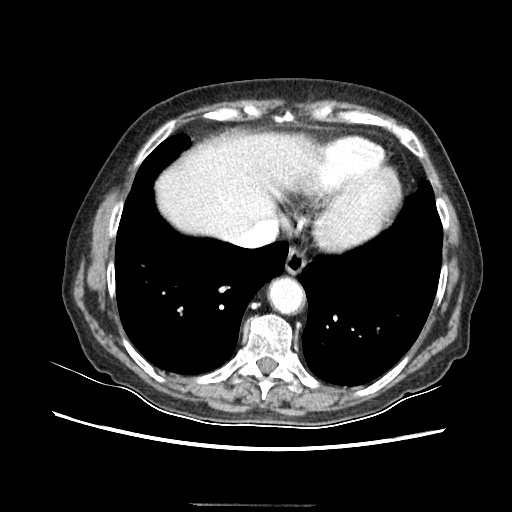

Original VENOUS CT scan

Full window (WL 1023.5, WW 4095 β†’ Low βˆ’1024, High +3071)

Lung window (WL -600, WW 1500 β†’ Low βˆ’1350, High +150)

Mediastinum window (WL 40, WW 400 β†’ Low βˆ’160, High +240)